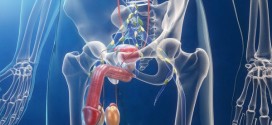

El plexo celíaco. Plexo nervioso simpático que se origina por el entrecruzamiento de las ramas eferentes de los ganglios semilunares. Se encarga de inervar los órganos abdominales. Para todas estas patologías la madre naturaleza nos regala sus dones más preciados para nuestra salud y recuperación y bienestar o al menos para tener una vida más digna… Información: Antes de nada …

El prostatismo. Estado general y mental provocado por enfermedades de la próstata, especialmente retención urinaria por hipertrofia del órgano. Si fuese de su deseo le podemos elaborar un plan trofológico personalizado para usted. Ver en prostatitis.

Los tumores malignos de próstata. Publicado en: binipatia.com Escrito por: Salvador Gregori y Abby Schaffner Etiquetas: sustancias súper nutritivas, tratamiento natural, reishi, vitamina D3 Resumiendo: La próstata es un órgano del sistema reproductor del varón. Es una glándula, con forma de castaña, colocada debajo de la vejiga y por delante del recto. La uretra (conducto por donde sale la orina) atraviesa la …

La próstata, suele dar problemas en los hombres en partir de los 47-50 años, no todos por igual eso que quede claro. La causa más numerosa de pacientes es por la hiperplasia benigna de próstata (HPB). El agrandamiento de la próstata, se refiere que se agranda (aumenta de tamaño), con lo cual hay los problemas para poder orinar o dificulta …

El carcinosarcoma de próstata. Publicado en: binipatia.com Escrito por: Salvador Gregori Escrivá y IJosh Bush Etiquetas: sustancias súper nutritivas, promover la salud verdadera, arsenal terapéutico alternativo Se trata del tumor maligno más frecuente en los seres humanos. En varones. Durante los primeros años de vida de una persona, las células normales se dividen más rápidamente para permitir el crecimiento. El cuerpo está …

La prostatitis. Infamación aguda o crónica de la próstata. Puede ser bacteriana aguda no asociada a sondaje se suele deber a los microorganismos urinarios habituales gran negativo (E. coli o klebsiella). En los casos asociados al sondaje pueden estar implicados bacilos gran negativos hospitalarios o enterococos. E. coli, klebsiella y proteus también causan prostatitis crónica. Las manifestaciones clínicas en la …